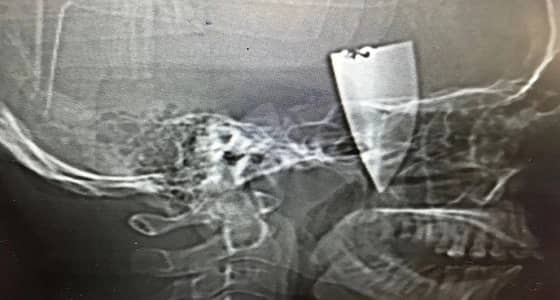

جراحة ناجحة لتثبيت صفيحة عنقية لمريض بحفر الباطن

خالد الضبيبي

فريق طبي بحفر الباطن يجري جراحة ناجحة لعشريني إصيب بكسر في العنق